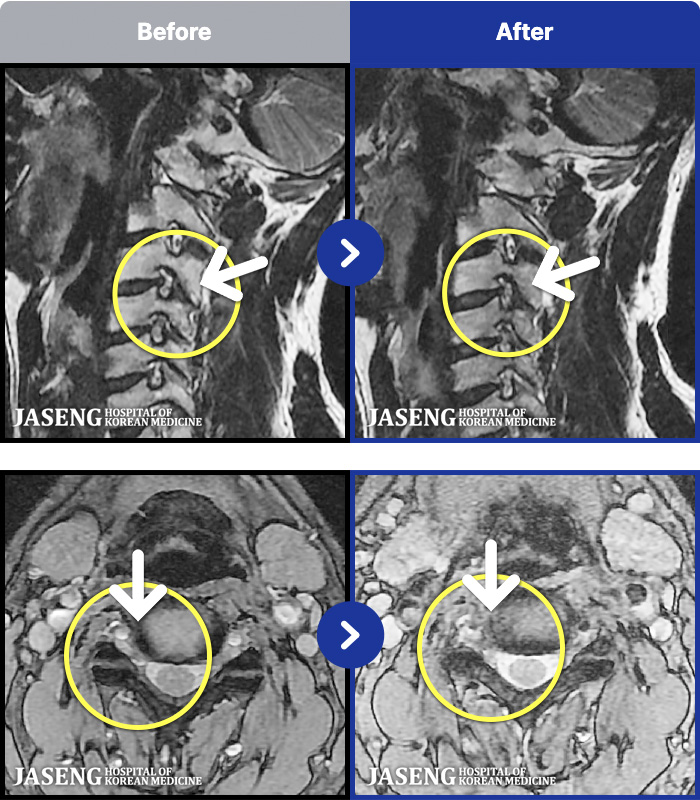

MRI ġ

MRI ũ ʸ Ȯϼ.